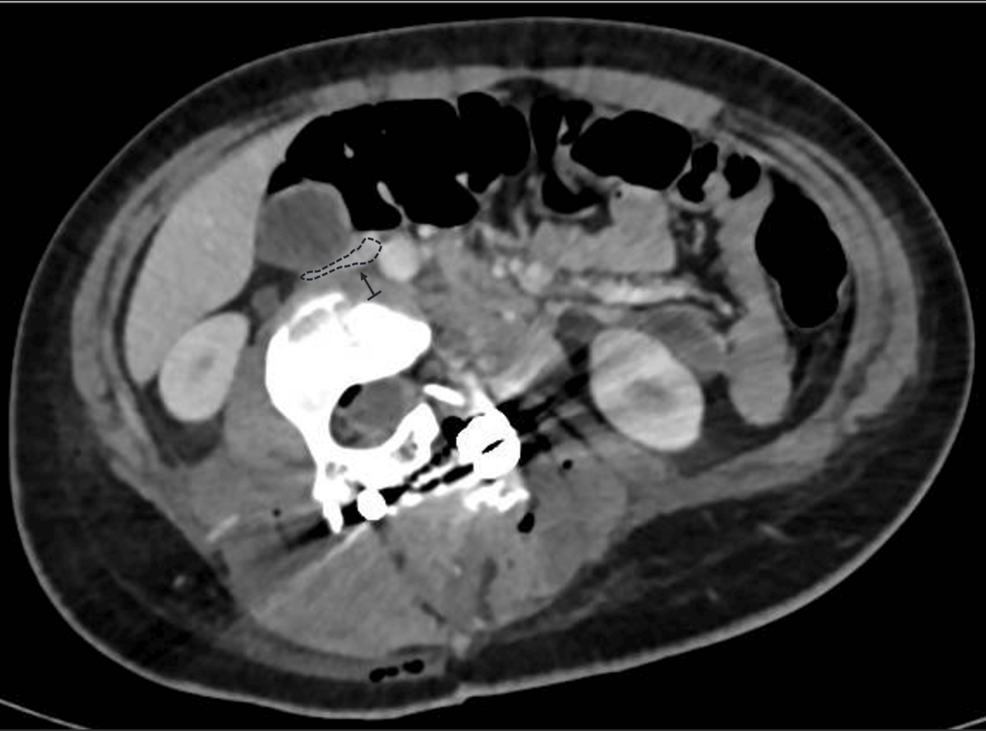

The patient remained hemodynamically stable postoperatively but exhibited persistent sinus tachycardia. Laboratory tests revealed a drop in hemoglobin to 9.2 g/dL (reference range: 12.0-14.0 g/dL) and an elevation in lactate to 11.6 (reference range: 6.3-18.9 mg/dL) mg/dL. She received a transfusion of 460 mL of packed red blood cells, which improved her hemoglobin to 12 g/dL. Postoperative CT angiography demonstrated substantial compression and displacement of the IVC, resulting in a 60% reduction in its lumen diameter at the L3 level (Figure 2). No evidence of thrombus or venous return obstruction was found. Furthermore, cardiology evaluation and echocardiography were performed to rule out other differential diagnoses that might explain the intraoperative hemodynamic changes, thereby excluding cardiac abnormalities. Furthermore, it was determined not to administer anticoagulation to the patient, despite the IVC compression, based on the absence of venous stasis or thrombotic findings on imaging. This conservative approach aligns with previous recommendations suggesting targeted intervention only when hemodynamic or thrombotic complications are evident [2,4].

In severe scoliosis, the anatomical positions of the great vessels are markedly altered, with the IVC and aorta frequently residing within the concavity of the spinal curve. This displacement effectively shortens their vascular length relative to a neutral alignment. Thus, during surgical maneuvers that involve rotation or lengthening of the spinal column, the anterior structures are exposed to significant tension and compression forces. In our case, where the hemivertebra was fused with adjacent vertebrae, forming a substantial mass similar to a vertebral block, it is plausible that derotation, by increasing lumbar lordosis and facilitating the anterior translation of the apical block vertebrae, reduced the distance between the spine and the anterior abdominal wall. Moreover, this derotation may have contributed to spinal elongation and stretching of the anterior soft tissues. These mechanisms are supported by postoperative CT angiography, which demonstrated that the correction maneuver increased the anterior spinal length, exerting significant traction on the IVC and reducing its lumen diameter by approximately 50% at the L3 level. Similar findings have been reported in studies examining vascular shifts during scoliosis correction, indicating that the position and diameter of the IVC and aorta are highly dependent on the severity and rigidity of the deformity [1,4].

Accurate preoperative imaging is essential for identifying potential risks in severe and rigid scoliosis surgery. Advanced imaging techniques such as CT angiography can map the spatial relationship between the spine and adjacent vascular structures, providing critical insights into the risk of compression or elongation during correction [4,11]. In this case, postoperative imaging confirmed significant compression and displacement of the IVC into the concavity of the deformity. While the absence of thrombus or obstruction at rest was reassuring, this finding emphasized the dynamic nature of vascular compression during surgical manipulation. Dynamic imaging modalities, such as upright CT or MRI, could offer additional information by simulating positional changes and their impact on venous return [4].